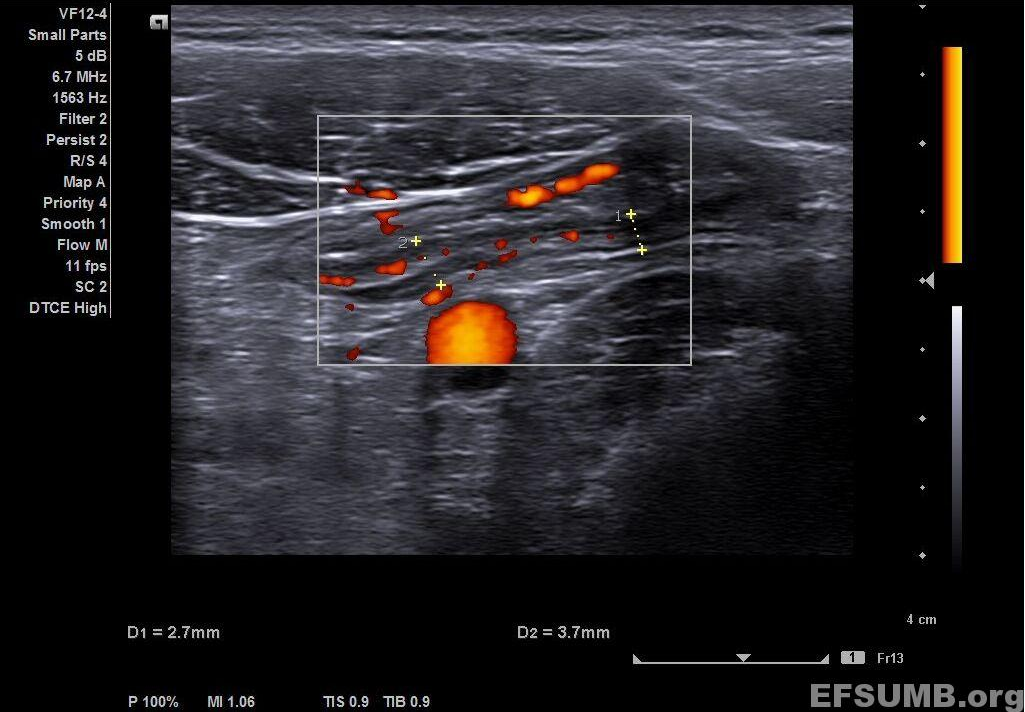

Longitudinal view of the sigmoid shows bowel wall thickness, about 3.7 mm, the most characteristic feature of inflammation; the bowel wall has the echo-stratification preserved. In addition, there is increased Doppler signal in the thickened bowel wall that can be also interpreted as a sign of active inflammation.